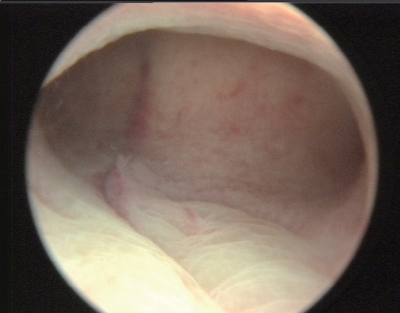

4)子宫腔粘连:按部位分为周围型和中央型子宫腔粘连;按性质分为内膜性、纤维肌性和结缔组织性子宫腔粘连;按严重程度分为轻度、中度和重度子宫腔粘连等(图3-12)。